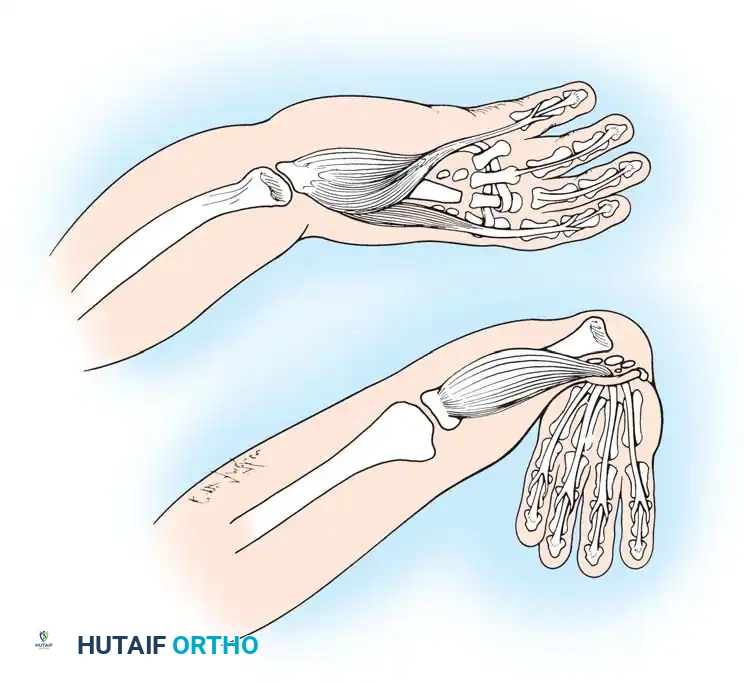

Fig. 76-1 Limb bud. The apical ectodermal ridge extends from anterior to posterior along the dorsal/ventral boundary of the growing limb bud. Proximal to the AER is the progress zone. Within the posterior mesoderm is the zone of polarizing activity. These centers are highly interconnected; limb patterning and growth depend entirely on their coordinated function.

By day 31 of gestation, the hand paddle becomes morphologically distinct. Through a genetically programmed process of cellular apoptosis (programmed cell death), the fissuring of the hand paddle is completed by day 36. The central rays form first, followed rapidly by the preaxial and postaxial digits. The formation of chondral elements, endochondral ossification, and the subsequent development of joints, musculature, and vascular networks follow in rapid succession. The entire embryological formation of the upper extremity is completed by the end of the 8th week of gestation.